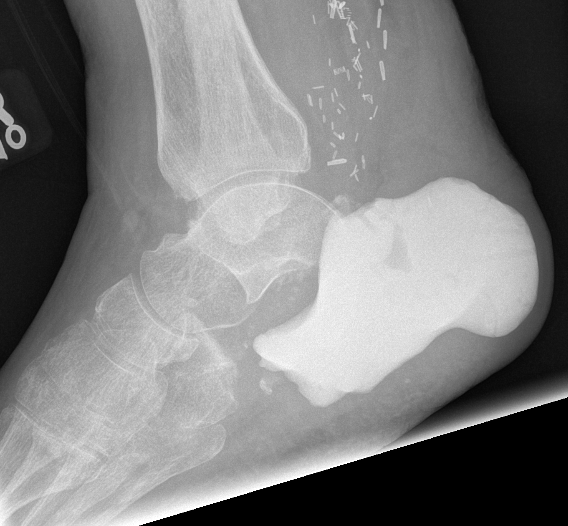

Unicameral Bone Cyst

Infrequent in foot

Calcaneum

Treat with curettage and bone graft